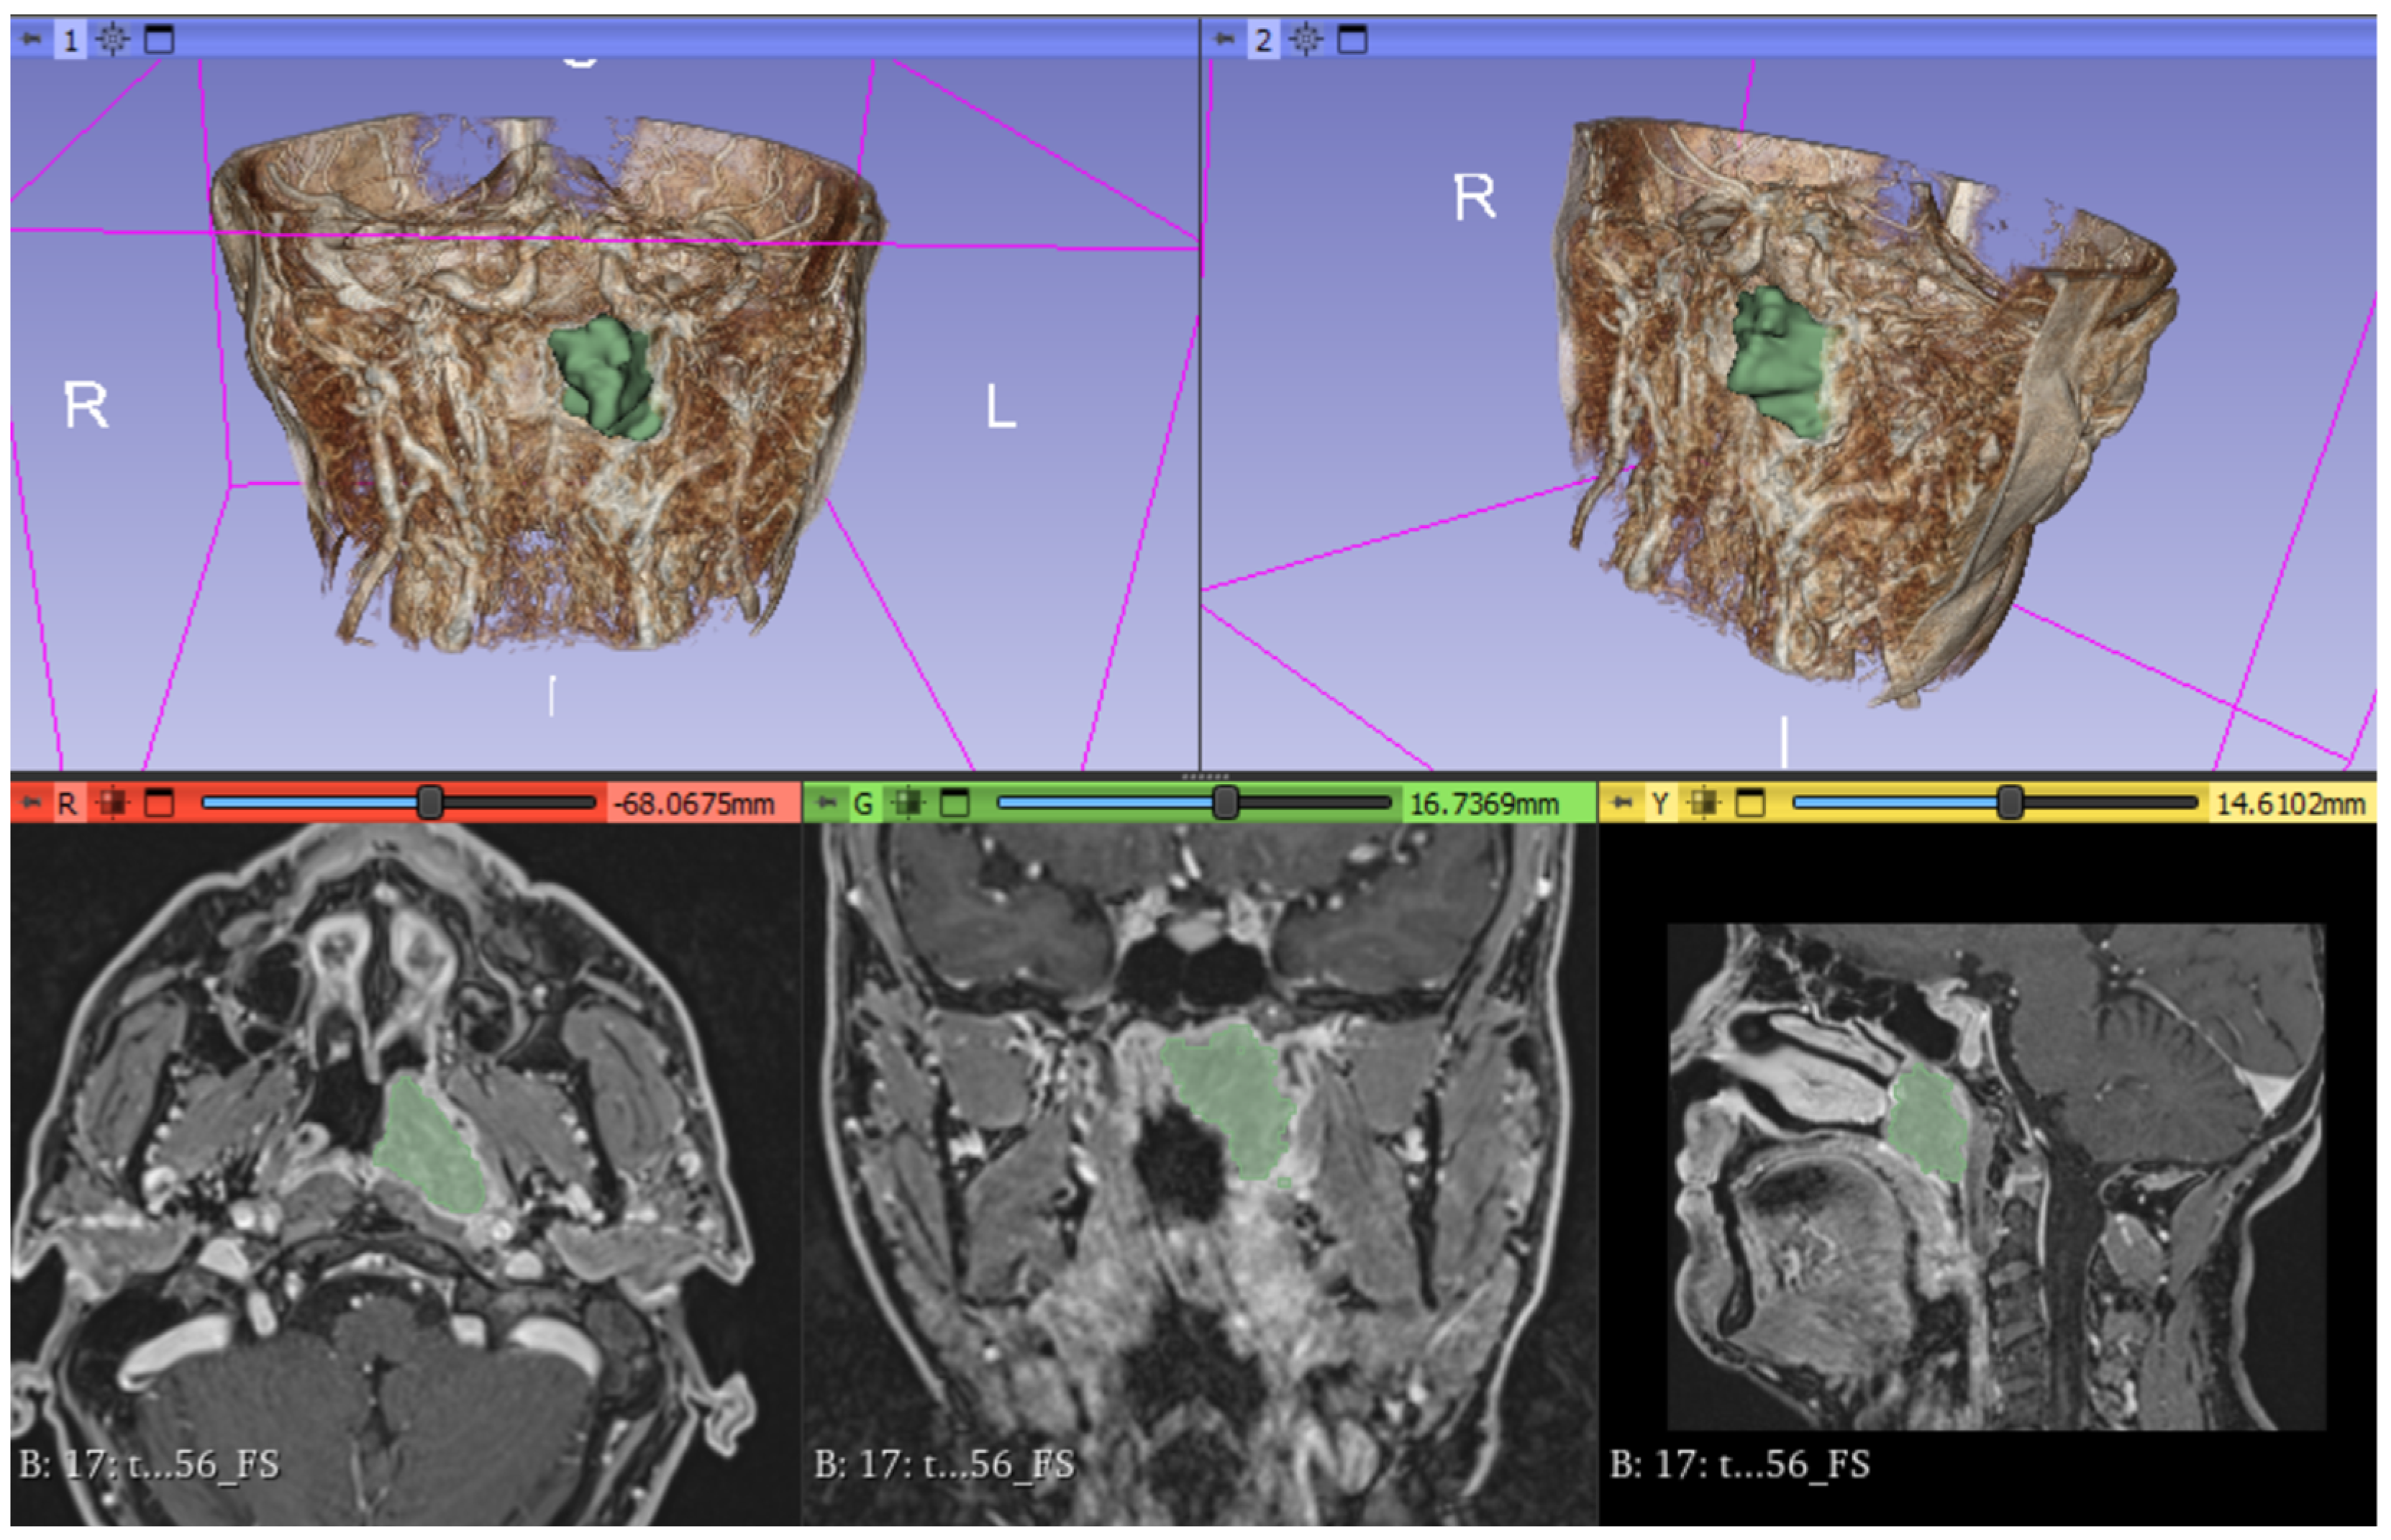

2.3. Image Analysis

Division into Groups Based on Imaging and Histological Examination